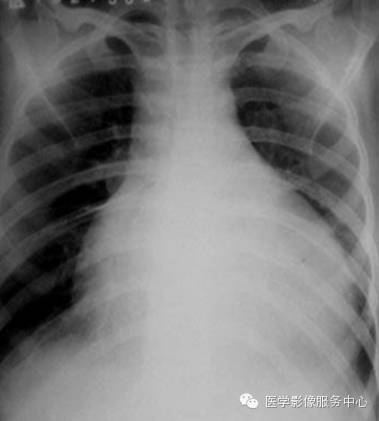

心包积液x线

心包积液(大量):x线:心外形重度增大,各弓弧度消失,呈烧瓶样改变;上

x线检查对少量的心包积液的诊断有限度.